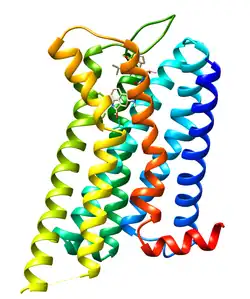

Dopamine receptor D2, also known as D2R, is a protein that, in humans, is encoded by the DRD2 gene. After work from Paul Greengard's lab had suggested that dopamine receptors were the site of action of antipsychotic drugs, several groups, including those of Solomon H. Snyder and Philip Seeman used a radiolabeled antipsychotic drug to identify what is now known as the dopamine D2 receptor.[5] The dopamine D2 receptor is the main receptor for most antipsychotic drugs. The structure of DRD2 in complex with the atypical antipsychotic risperidone has been determined.[6][7]

D2R conformers are equilibrated between two full active (D2HighR) and inactive (D2LowR) states, while in complex with an agonist and antagonist ligand, respectively.

The monomeric inactive conformer of D2R in binding with risperidone was reported in 2018 (PDB ID: 6CM4). However, the active form which is generally bound to an agonist, is not available yet and in most of the studies the homology modeling of the structure is implemented. The difference between the active and inactive of G protein-coupled receptor is mainly observed as conformational changes at the cytoplasmic half of the structure, particularly at the transmembrane domains (TM) 5 and 6. The conformational transitions occurred at the cytoplasmic ends are due to the coupling of G protein to the cytoplasmic loop between the TM 5 and 6.[19]

It was observed that either D2R agonist or antagonist ligands revealed better binding affinities inside the ligand-binding domain of the active D2R in comparison with the inactive state. It demonstrated that ligand-binding domain of D2R is affected by the conformational changes occurring at the cytoplasmic domains of the TM 5 and 6. In consequence, the D2R activation reflects a positive cooperation on the ligand-binding domain.

In drug discovery studies in order to calculate the binding affinities of the D2R ligands inside the binding domain, it's important to work on which form of D2R. It's known that the full active and inactive states are recommended to be used for the agonist and antagonist studies, respectively.

It was observed that D2R exists in dimeric forms or higher order oligomers.[22] There are some experimental and molecular modeling evidences that demonstrated the D2R monomers cross link from their TM 4 and TM 5 to form dimeric conformers.[23][24]